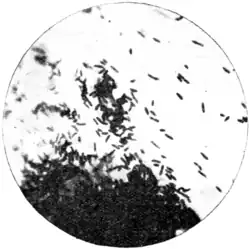

The plague bacterium (Fig. 66), as seen in smearings or scrapings from the pulp of the buboes, or from any of the inflamed lymphatic glands, or from the viscera, is a short, thick cocco-bacillus (1.5 to 2 μ and 0.5 to 0.7 μ) with rounded ends, very like that of chicken cholera. Gordon says it has one terminal flagellum. A capsule, according to the same observer, or the appearance of a capsule, can generally be made out, especially in those bacilli which are present in the blood. The bacillus is readily stained by aniline dyes, the extremities taking on a deeper colour than the interpolar part. It is usually decolorized by Gram.

Fig. 66.—Bacillus of plague in chains showing polar staining. From a young culture in bouillon, x 1,000. (Muir and Ritchie.)